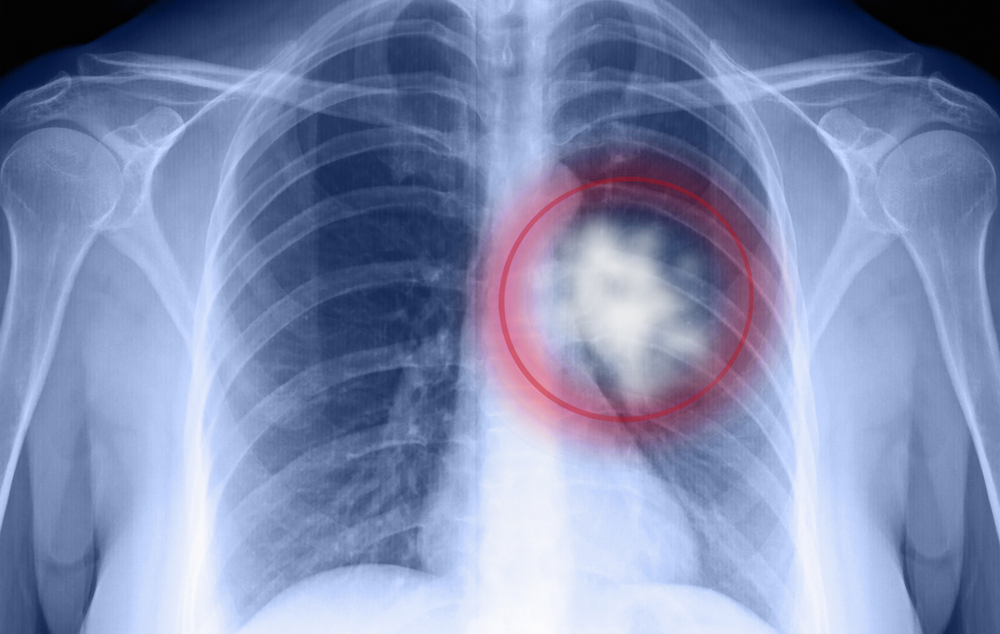

បើគ្នាយើងជក់បារីកាន់តែច្រើន កត្តាប្រឈមកើតជំងឺមហារីកសួត និងជំងឺសួតរ៉ាំរ៉ៃ ក៏កើតមានខ្ពស់ដែរ។ ការជក់បារី មិនថាតិចឬច្រើន សុទ្ធតែមិនមានសុវត្ថិភាពចំពោះសុខភាពសួត ដូចនេះជាការល្អកុំជក់បារី។

ជំងឺមហារីកសួតភាគច្រើនកើតឡើងដោយសារការជក់បារី។ ក្រោយពីឈប់ជក់បារី កត្តាប្រឈមនៃការកើតជំងឺនេះ ក៏ធ្លាក់ចុះច្រើនដូចគ្នា។ បើយើងឈប់ជក់បារីបានដប់ឆ្នាំ កត្តាប្រឈមនឹងធ្លាក់ចុះពាក់កណ្ដាល នៃលទ្ធភាពដែលយើងប្រឈមខ្ពស់កន្លងមកបើយើងនៅបន្តជក់បារី។ កត្តាប្រឈម កើតជំងឺមហារីកសួត កាន់តែថយចុះ បើយើងឈប់ជក់បារីកាន់តែយូរ។